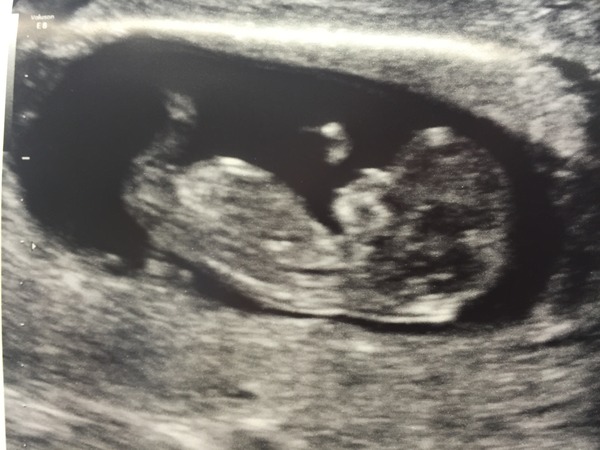

11+3 they confirmed my date as exactly right. NT measurement was really small just to wait for result to come back.

Wow cookie! Amazing picture, so clear. Smile

Becks lovely scan pic. It's amazing how big and how much detail there is at such an early stage.

Cookies fab scan. Wow very rare to be bang on for dates I'm always about 6 days out.